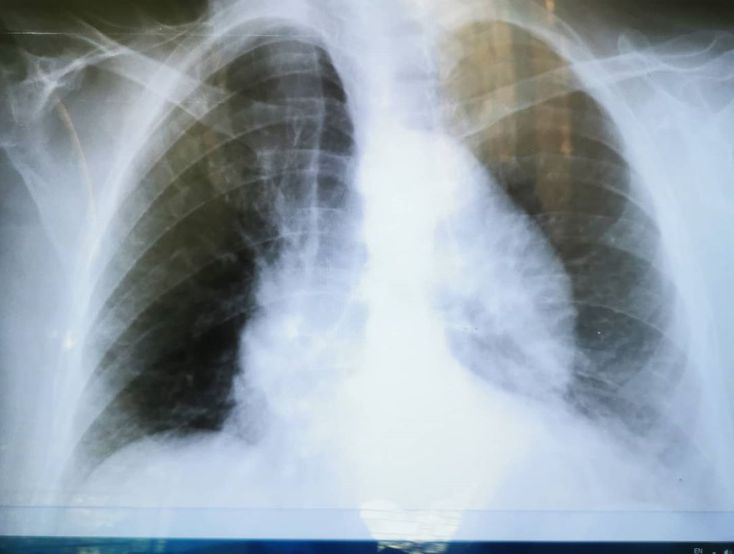

80 year old female patient history of HTN and hyperlipidemia, complains of dry cough since 3 months, night sweats,no weight loss, SOB with effort. This is her CXR, what's your differential diagnosis?

Low KV CXR, heart failure and cardiomyopathy. And aortic aneurysm is ddx.

cxr findings inconsistent with TB. but we sent AFB smear of sputum.